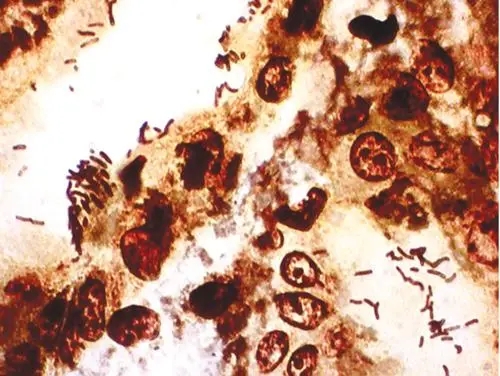

HK2